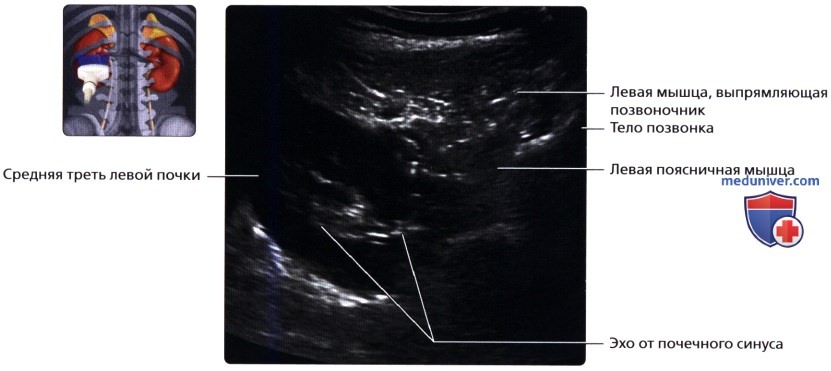

Сначала исследуют почки в продольном направлении (поясничная область), затем изучают поперечные и косые срезы, перемещая датчик на переднюю и боковые поверхности живота. При этом пациента просят поочередно повернуться на правый и левый бок. Такая техника позволяет определить локализацию (месторасположение) почек, их размеры и форму, оценить состояние паренхимы, почечных синусов, чашечек и лоханок.

Для определения подвижности почек и улучшения визуализации органов при каждом изменении положения тела врач просит больного вдохнуть и на несколько секунд задержать дыхание. На вдохе почки опускаются из-под реберной дуги и просматриваются намного лучше. УЗИ почек стоя делают при подозрении на нефроптоз (опущение одной или обеих почек).

а) Анатомия почек:

3. Внутренняя структура:

• Почки можно рассматривать как полый орган, просвет которого занят жировой тканью, почечной лоханкой, чашечками, сосудами и нервами

• Ворота почки: сюда подходят артерия и вена и выходит мочеточник

• Почечная лоханка: расширение верхнего конца мочеточника в виде воронки:

о Собирает мочу от больших чашечек (2 или 3), каждая из которых в свою очередь собирает мочу от малых чашечек (2-4)

• Почечный сосочек: точечная верхушка почечной пирамиды, содержащей собирательные трубочки, выделяющие мочу

о Каждый сосочек открывается в малую чашечку

• Корковое вещество почки: периферическая часть, содержит почечные (клубочки, сосуды), проксимальные части собирательных трубочек и петли Генле

• Мозговое вещество почки: внутренняя часть, содержит почечные пирамиды, дистальные части собирательных трубочек и петли Генле

б) Лучевая анатомия почки:

1. Обзор:

• Забрюшинные структуры бобовидной формы с четким контуром, смещающиеся при дыхании